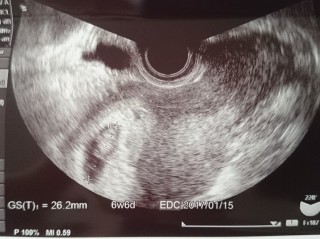

無事に胎芽・心拍を確認できました!

前回の5w5dでは胎嚢と卵黄嚢のみでしたが、2週間でしっかりと赤ちゃんが見えて感動しました!

胎芽13.4mm!

前回の妊娠は胎嚢確認後の流産だったので、まだまだ不安は大きいですが一歩先に進めてホッとしています。